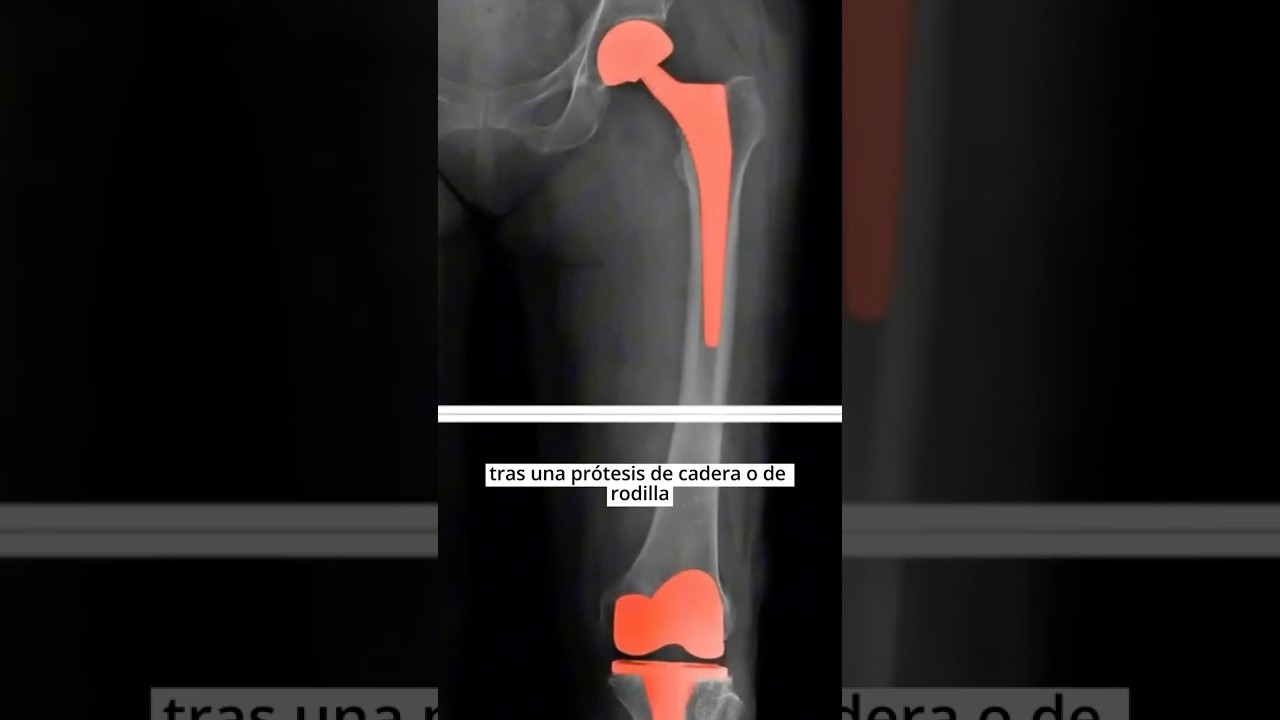

Antes de profundizar en los trabajos incompatibles con prótesis de cadera, es importante entender qué implica esta intervención. Una prótesis de cadera es un dispositivo médico que se utiliza para reemplazar una articulación de cadera dañada, generalmente debido a condiciones como la artritis o una fractura. La cirugía de reemplazo de cadera puede mejorar significativamente la movilidad y reducir el dolor, pero también conlleva ciertas restricciones en la actividad física y el tipo de empleo.

Existen diferentes tipos de prótesis de cadera, incluyendo prótesis totales y parciales. La elección entre estos tipos depende de la extensión del daño en la cadera y las necesidades específicas del paciente. Las prótesis totales reemplazan tanto el acetábulo como el fémur, mientras que las parciales solo sustituyen una de las partes. La rehabilitación postoperatoria es crucial para asegurar una recuperación adecuada y una adaptación exitosa a la prótesis.